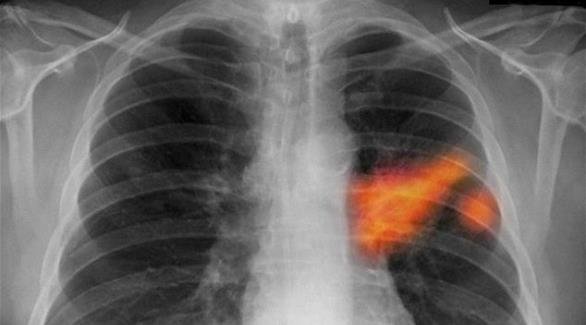

دراسة: سرطان الرئة قد يظل كامناً لمدة 20 عاماً